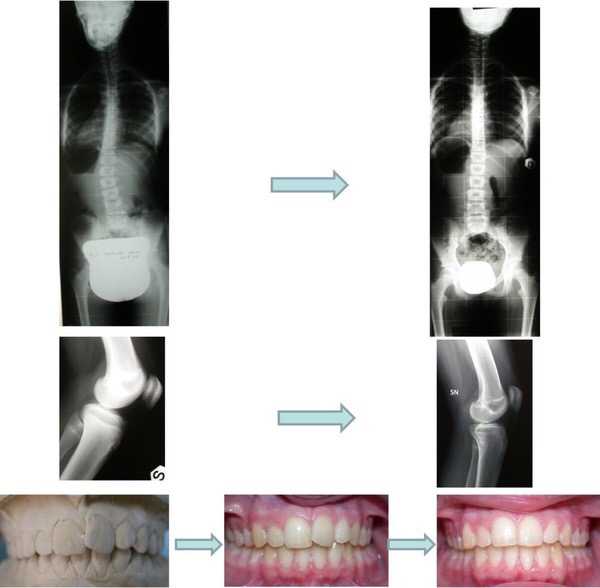

До недавнего времени в медицине считалось, что достичь симметричного тела невозможно, однако наука не стоит на месте. Ещё недавно считавшиеся нетрадиционными методами лечения ортокраниодонтия и методика Starecta позволяют добиться идеальной симметрии тела через воздействие на стоматологическую систему организма. «Всего лишь» регулируя положение челюстей, оба альтернативных метода позволяют приблизиться к максимально возможной симметрии и улучшить качество здоровья и жизни.

ортодонтия, работа проф. Стефанелли (Италия), www.osstefanelli.com

симметрия лицевых структур, достигнутая методом Starecta«Что бы ни считалось красотой, в своей основе оно имеет гармонию и единство», — сказал один католический священник. Древнегреческими философами красота и симметрия воспринималась как явление объективное и онтологическое по своей сути, связанное с совершенством Универсума и пониманием космоса как гармоничного миропорядка. Поэтому становится так понятно врожденное человеческое стремление к красоте и симметрии — в его основе лежит наше желание вернуться к задуманному Вселенной природному эталону, тяга к изначальной гармонии и целостности…